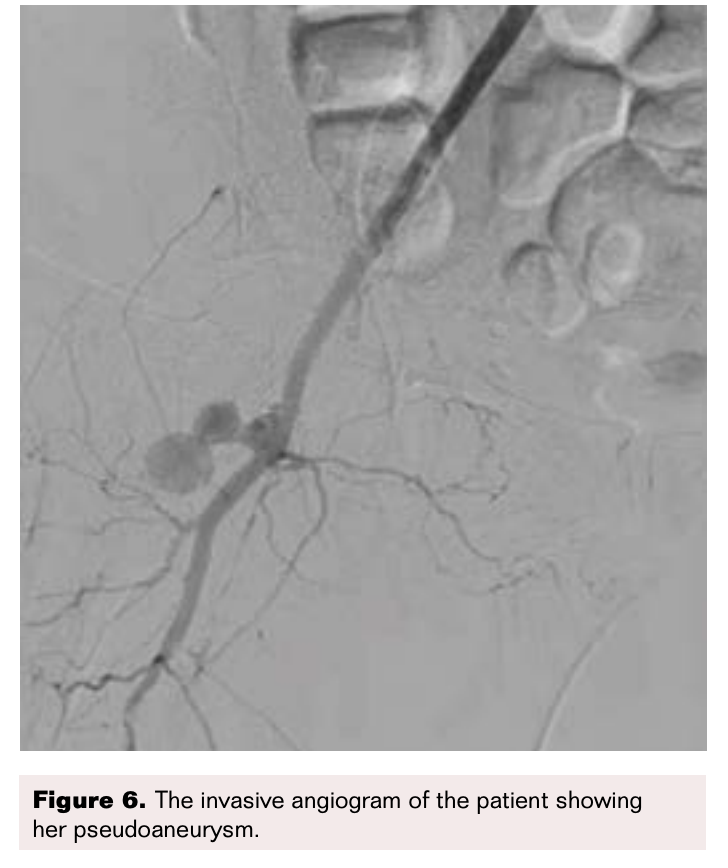

At SCTIMST, ultrasonic guided manual compression was performed for 60 minutes. However, flow into the pseudoaneurysm continued. The patient was then taken for percutaneous coil insertion under fluoroscopic guidance (Cook Nestor; coils 0.035). A left femoral puncture was taken and a check angiogram was performed (Figure 6). This revealed a bilobed pseudoaneurysm arising from the right common femoral artery. Through a guide catheter, Cook coils were instilled using a guidewire (Figure 7). However the check angiogram showed continued blood flow into the aneurysm (Figure 8). Hence it was decided that the sac would be closed by instillation of thrombin percutaneously.